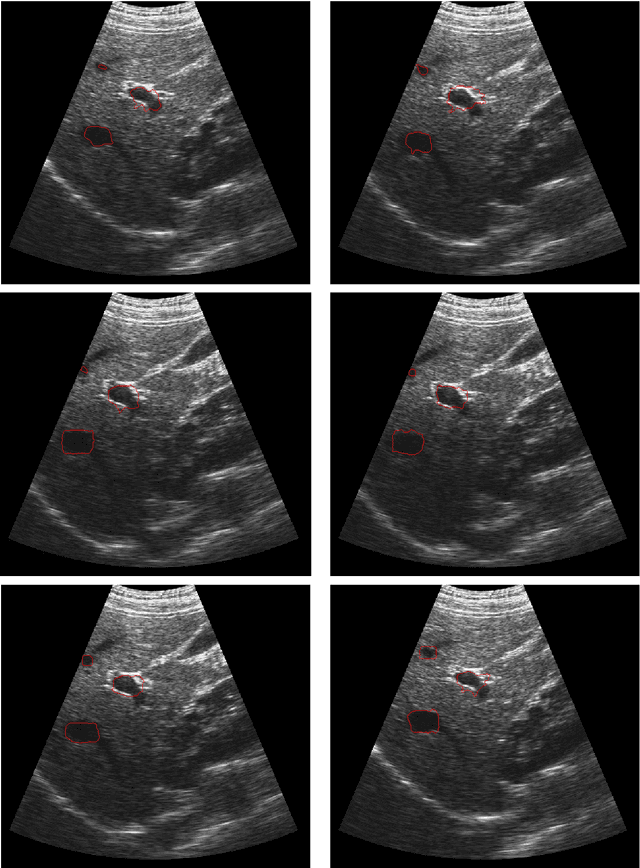

Abstract:In this paper we present a new method for motion tracking of tumors in liver ultrasound image sequences. Our algorithm has two main steps. In the first step, we apply mean shift algorithm with multiple features to estimate the center of the target in each frame. Target in the first frame is defined using an ellipse. Edge, texture, and intensity features are extracted from the first frame, and then mean shift algorithm is applied to each feature separately to find the center of ellipse related to that feature in the next frame. The center of ellipse will be the weighted average of these centers. By using mean shift actually we estimate the target movement between two consecutive frames. Once the correct ellipsoid in each frame is known, in the second step we apply the Dynamic Directional Gradient Vector Flow (DDGVF) version of active contour models, in order to find the correct boundary of tumors. We sample a few points on the boundary of active contour then translate those points based on the translation of the center of ellipsoid in two consecutive frames to determine the target movement. We use these translated sample points as an initial guess for active contour in the next frame. Our experimental results show that, the suggested method provides a reliable performance for liver tumor tracking in ultrasound image sequences.